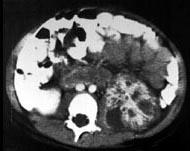

问题 男,5岁,有尿路感染伴急性发热,CT增强扫描如图所示,最可能诊断为 ( )

选项 A、左侧黄色肉芽肿性肾盂肾炎 B、左侧慢性肾盂肾炎 C、左侧肾脓肿 D、左侧急性肾盂肾炎 E、左侧肾炎

答案 D